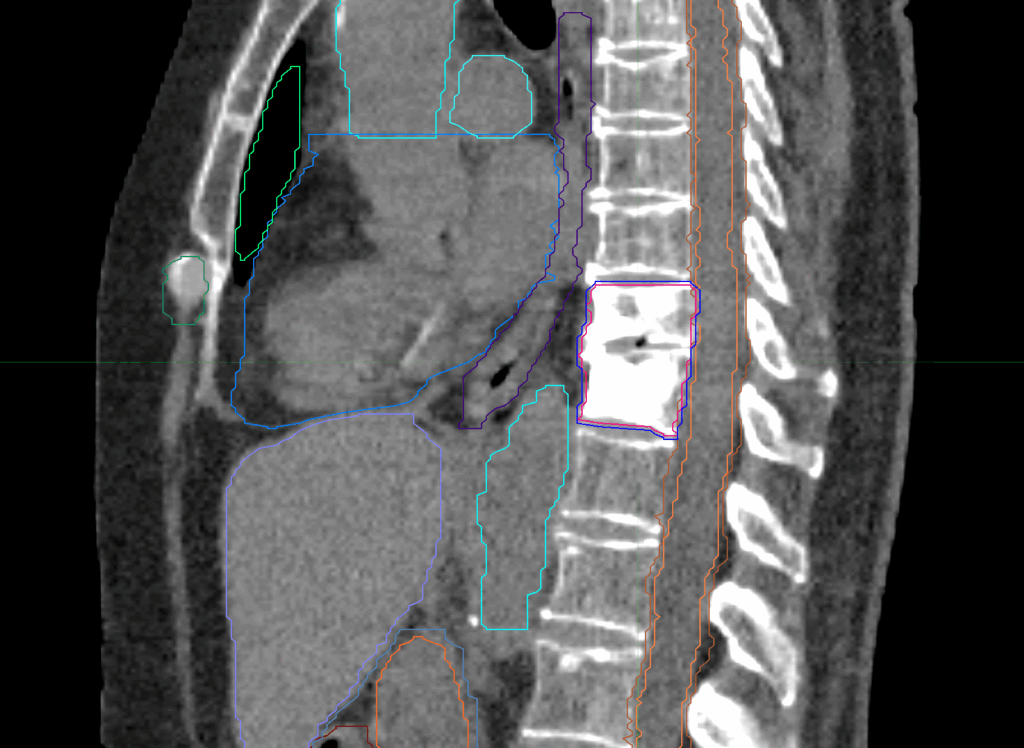

Planning CT Images

Treatment Planning Highlights

PTV(s) Volume

PTV, 45.5 cc

Dose Distributions

- Prescription to the

75.6% isodose line - Max. dose 35.71 Gy

New Conformality Index (nCI)

nCi = 1.33